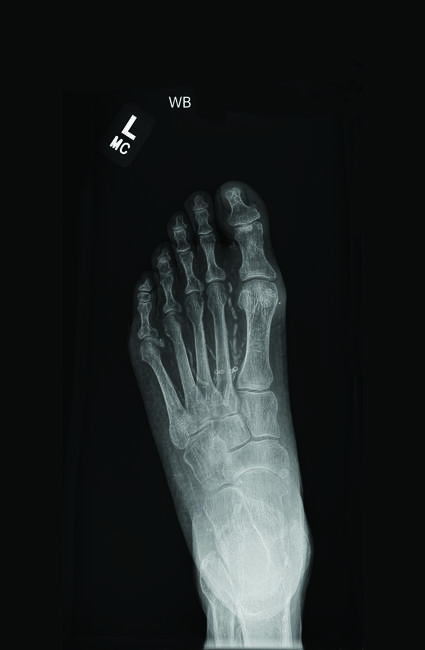

Medial arterial calcification (MAC) is a chronic vascular condition commonly observed in individuals with diabetes mellitus.1 Although once thought to have little clinical implication, MAC is now known an independent contributor to peripheral artery disease, imparting significant morbidity and mortality.2,3 Deposits of calcium and phosphate in the medial layer of the arterial wall are hallmark characteristics of MAC.4 Distinct from intimal calcification, which is associated with atherosclerosis and tends to affect the larger arteries, MAC is most frequently observed in the small- and medium-sized peripheral arteries.3 Specifically found in the smooth muscle of the vessel, MAC contributes to disruption of the elastin layer with subsequent calcification, ultimately leading to arterial stiffness as calcifications progress.3,5 In contrast, intimal calcifications are linked to inflammation and bone-like formation within the atherosclerotic plaque.3 Whereas intimal calcifications typically appear as patchy areas of calcification within the lumina of the internal elastic lamina, MAC manifests as continuous areas of calcification, often visualized as parallel lines or “railroad tracks” on plain film radiographs.2,3

Several described methods assess the presence and severity of lower limb calcifications, including using plain film radiographs and computed tomography scanning. Guzman and colleagues evaluated and scored the extent of tibial artery calcification on computed tomography scans in 229 patients. Of those studied, they found that those with critical limb ischemia had the greatest tibial artery calcification scores and those with a high tibial artery calcification score were at increased risk for major amputation, with calcification scoring predicting amputation better than ankle-brachial index.19 In 2020, Ferraresi and team published on a novel scoring system for assessing medial arterial calcification on plain film radiographs. The scoring system entails measurement of calcification at 5 sites in the foot:

- the dorsalis pedis artery from the ankle joint to the metatarsals;

- the lateral plantar artery from its bifurcation of the posterior tibial artery to the distal plantar arch;

- the first metatarsal artery from its proximal origin to the metatarsophalangeal joint;

- the first toe artery medial or lateral; and

- other toe arteries from the metatarsophalangeal joint to the distal toe.

They assessed each site for the presence of MAC and scored them as 0 or 1 point, with a total possible score of 5 points.23 The authors validated their scoring system through comparison to angiographic findings, noting a high sensitivity and specificity of the MAC score, and finding MAC score to be an independent predictor of major adverse limb events, including major amputation or re-intervention, defined as both revisional revascularization as well as unplanned podiatric surgical re-interventions, in patients with chronic limb-threatening ischemia.23

Although the exact prevalence of MAC amongst those with diabetes mellitus is unknown, studies suggest rates from 17% to 68%.1,31 Nearly 12% of individuals in the United States have diabetes mellitus, of which approximately one-quarter to one-third are at risk to develop a foot ulceration during their lifetime. Thus, it is imperative to understand contributing factors to diabetic foot disease and impaired healing.32-34 Ordering plain film radiographs is standard practice when assessing diabetic foot ulcerations. Through simple assessment of a pedal calcification score on these X-rays, one can gain valuable prognostic insight, perhaps arguably greater than that of ABIs in those with vascular calcifications.

While the etiology of DFU is complex and multifactorial, MAC in those with DFU demonstrates itself a significant predictor of outcomes, associated with slower wound healing, higher likelihood for multiple podiatric surgical interventions, poorer outcomes after endovascular revascularization procedures, increased likelihood of persistent ischemia, and increased rates of major amputation and death. Observation of MAC on plain film radiographs offers significant prognostic information that one should not overlook. Calculation of a pedal MAC score may serve as a reliable measure of judging calcification severity, which one can correlate to predict outcomes. For the best chance at limb salvage, a multidisciplinary team approach is imperative, with consideration for early vascular referral to optimize wound healing in this complicated patient population.